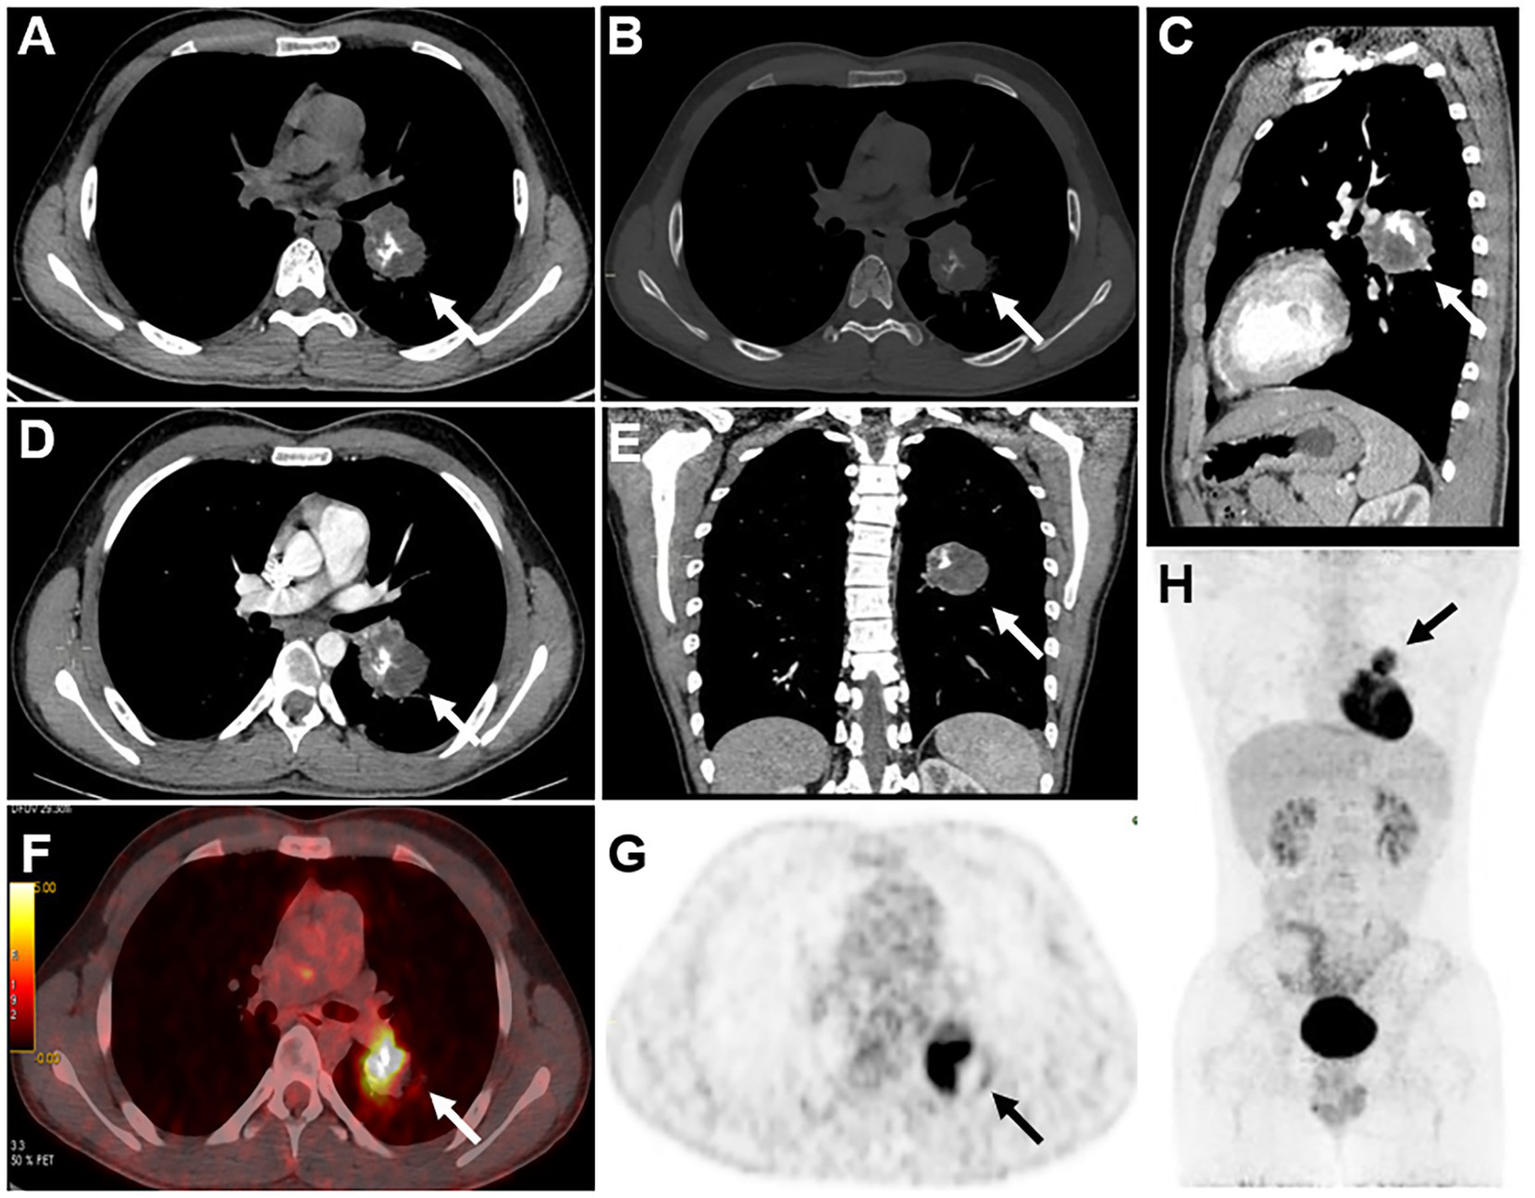

A 17-year-old male patient had a cough and hemoptysis for 20 days, a mass in the lower lobe of the left lung was observed during the examination of an external hospital, therefore he came to visit our hospital. His medical history and family history were negative. Laboratory examination demonstrated no abnormalities in the examination of lung cancer tumor markers CA125, cyfra21-1, NSE, SCC, or CEA. In CT images, the lesion appeared as a soft tissue density mass at the lateral bronchus of the dorsal segment of the left inferior lobe, which also grew towards the lumen of the left interlobular pulmonary artery. It was a spherical-like mass with a maximum diameter of 4.2 cm and uneven density. In addition, there were small striations and areas of bone density to the right of the center, and its postero-lateral side appeared hypodense. The mass was ill-defined, with no abnormal density in the surrounding lung tissue, no clear enlarged lymph nodes in the mediastinum, and no abnormal density changes at the rib scan level. The enhancement scan revealed mild to moderate heterogeneous enhancement with poorly defined boundaries and no enhancement in the cystic region. 18F FDG PET/CT images demonstrated a tumor in the left lower lobe of the lung with an unevenly increased metabolic rate and increased mediastinal lymph node metabolism with no other systemic PET/CT abnormalities observed, which indicates the high potential of lymph node metastasis and no distant metastasis. This lesion exhibits the obvious absence of elevated metabolism in its postero-lateral side, where the density was relatively low in contrast-enhanced CT. Combining CT and PET/CT assessments, the initial preoperative TNM staging was determined to be T2N1M0.

Figure 2

CT scans of the mediastinal window (A), bone window (B), and sagittal mediastinal window (C) revealed a mass-like soft tissue density shadow in the dorsal segment of the lower lobe of the left lung. The mass had an irregular sphere-like margin, uneven density within the mass, and irregular eccentric ossification or calcification. In addition, axial (D) and coronal (E) enhanced CT images also revealed a heterogeneous mass with no enhancement in the cystic portion. 18F-FDG PET/CT revealed uneven increased metabolism of the mass in the lower lobe of the left lung, with barely absent uptake in its postero-lateral side (F,G), and the area in the postero-lateral side with increased metabolic activity in lymph nodes was also observed, which also appears hypodense on contrast-enhanced CT. No elevated metabolic activity was observed in other areas on the PET/CT scan (H). Based on a comprehensive evaluation of CT and PET/CT findings, the initial staging before surgery was T2N1M0.